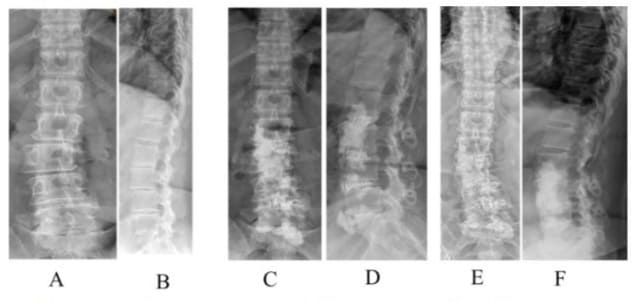

Figure 11: A 75-year-old female with degenerative scoliosis of 43° and lumbar lordosis of 36° (A, B) underwent L2/4 OIBC. Immediate postoperative scoliosis was 5° and lumbar lordosis was 48° (C, D). She underwent L1/2 PIBC 41 days later. (E, F), which was wellmaintained at the final follow-up at one year (G, H).

Additional PIBC

This study performed additional PIBC in four patients (2 in the OIBC group and 2 in the PIBC group) (Figure 11) immediately cranial to the previous IBC due to symptomatic junctional scoliosis with radiculopathy.